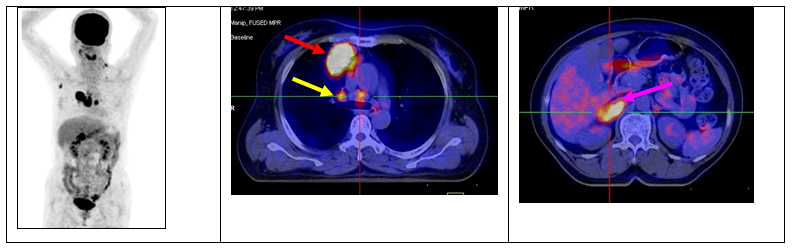

Ca lâm sàng 1: Bệnh nhân nữ, 53 tuổi, chẩn đoán: Ung thư phổi (giải phẫu bệnh: ung thư biểu mô tuyến), chỉ định chụp PET/CT để xác định giai đoạn bệnh trước điều trị:

Hình 1: Khối u ác tính phổi phải (mũi tên đỏ) di căn hạch trung thất (mũi tên vàng), di căn tuyến thượng thận phải (mũi tên tím).